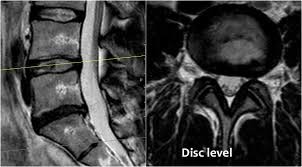

چنانچه بیمار علائم محوری در ستون فقرات و یا علائم انتشاری در اندام ها داشته باشد پزشک با شک به بیرون زدگی دیسک بیمار را معاینه کرده و در صورت تایید تشخیص تصویربرداری درخواست می شود که شامل: عکس ساده از ستون مهره ها جهت بررسی فاصله بین مهره ها و سرخوردگی و تغییرات آرتروزی است که گاها جهت دقت بیشتر سی تی اسکن انجام میشود و همچنین ام ار ای جهت بررسی بافت نرم یعنی دیسک ها و نخاع و رشته های عصبی است که فتق دیسک و میزان بیرون زدگی آن به دقت مشخص می گردد.

یکی از روشهای اینترونشنال در درمان دیسک کمر و گردن با لیزر، کاهش فشار داخل دیسک بیرون زده از راه پوست به کمک لیزر (Percutaneous Laser Disc Decompression) PLDD نام دارد. در مشکل بیرون زدگی دیسک فشار داخل دیسک افزایش یافته است. لذا در این تکنیک تحت هدایت دستگاه رادیولوژی (فلوروسکوپ) یک سوزن از پوست و عضلات عبور کرده و به مرکز دیسک وارد می شود و سپس از داخل سوزن یک فیبر نازک لیزر عبور کرده و نوک فیبر نوری در هسته مرکزی دیسک قرار می گیرد و با استفاده از لیزر قسمتی از بافت هسته دیسک تبخیر شده و موجب کاهش فشار داخل دیسک شده لذا حجم و اثر فشاری دیسک بیرون زده کاهش یافته و فشار از روی عصب برداشته می شود. جهت توضیح این تکنیک ابتدا باید مفهوم فتق دیسک و مشکلات آن را بدانید و سپس تکنیک لیزر دیسک و ملاحظات آن توضیح داده می شود: